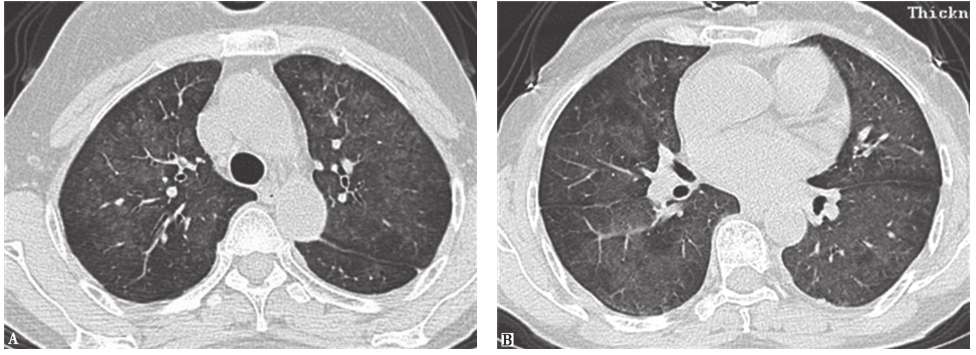

图7 RB-ILD胸部CT表现

男性患者,41岁,胸腔镜肺活检病理证实为呼吸性细支气管炎伴间质性肺疾病。CT示两肺弥漫分布小叶中心型小结节影、周围支气管管壁增厚

图9亚急性过敏性肺炎胸部CT表现

胸部CT示两肺弥漫性边界不清的小结节影

图10慢性过敏性肺炎胸部CT表现

胸部CT示两肺磨玻璃影、蜂窝肺形成